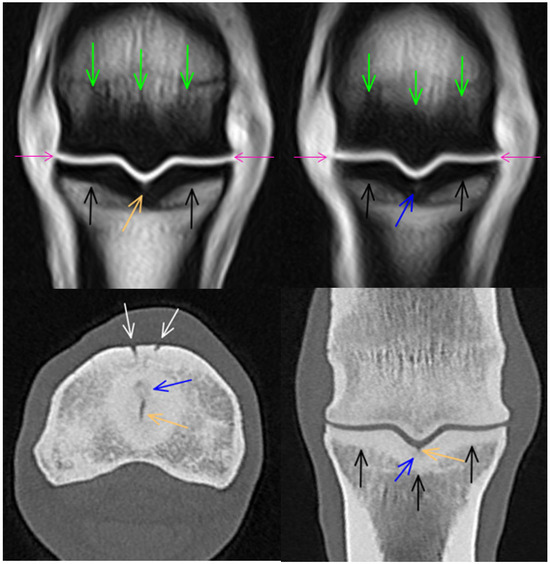

3.4. Soft Tissues